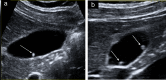

Gallbladder polyps are protuberances of the gallbladder wall projecting into the lumen. They are usually incidentally found during abdominal sonography or diagnosed on histopathology of a surgery specimen, with an estimated prevalence of up to 9.5% of patients. Gallbladder polyps are not mobile and do not demonstrate posterior acoustic shadowing; they may be sessile or pedunculated. Gallbladder polyps may be divided into pseudopolyps and true polyps. Pseudopolyps are benign and include cholesterolosis, cholesterinic polyps, inflammatory polyps, and localised adenomyomatosis. True gallbladder polyps can be benign or malignant. Benign polyps are most commonly adenomas, while malignant polyps are adenocarcinomas and metastases. There are also rare types of benign and malignant true gallbladder polyps, including mesenchymal tumours and lymphomas. Ultrasound is the first-choice imaging method for the diagnosis of gallbladder polyps, representing an indispensable tool for ensuring appropriate management. It enables limitation of secondary level investigations and avoidance of unnecessary cholecystectomies.